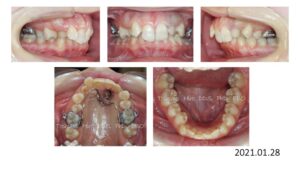

最初に急速拡大装置を装着して上顎骨の拡大を開始。

目的のところまで拡大したあと、上顎にブラケットを付け、開始から9ヶ月後に急速拡大装置を除去、下顎にもブラケットを装着し、

無事、治療が終わりました。

急速拡大開始からマルチブラケットが外れるまでの動的治療期間は 3年です。

この患者さんは、現在、治療後10年経過していますが、今も良い状態を保っています。